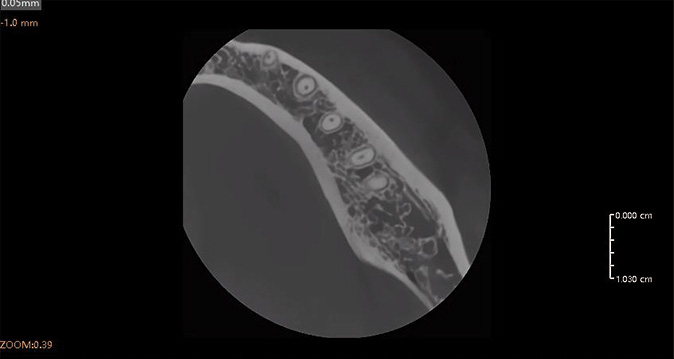

5 x 5 cm

Campo focalizado para endodoncia y precisión de implante único.

El FOV ultrapequeño garantiza una exposición mínima a la radiación, perfecto para imágenes pediátricas, tratamiento de conducto radicular y evaluación de implantes únicos.

Resolución de Voxel HD de 50 µm

La resolución de vóxel ultrafina garantiza una nitidez de grado clínico para diagnósticos de precisión y planificación quirúrgica.